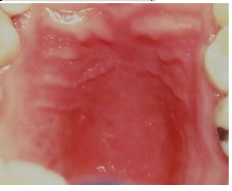

candidiasis oral manifestations- erythematous or atrophic candidiasis

- most commonly seen during early stages of HIV (in combination with pseudomembranous form)